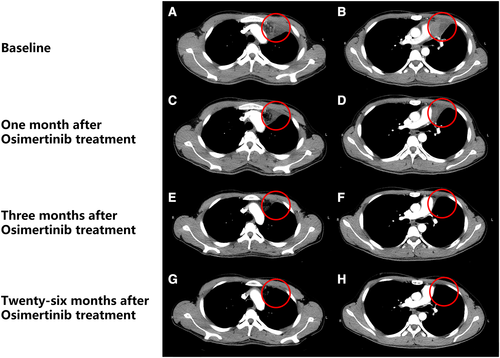

患者2017年6月份检测到EGFRT790M胚系突变(并携带L858R体系突变),随后于2017年6月28日开始口服奥希替尼治疗。一个月后,患者的心包和左胸腔积液被吸收,肺淋巴结变小,三个月后,患者的症状进一步改善,根据标准,临床反应被分类为完全缓解(CR)。患者接受奥希替尼治疗30个月(至2019年12月),并没有出现与药物有关的重大不良事件。

▲奥希替尼治疗后的影像图